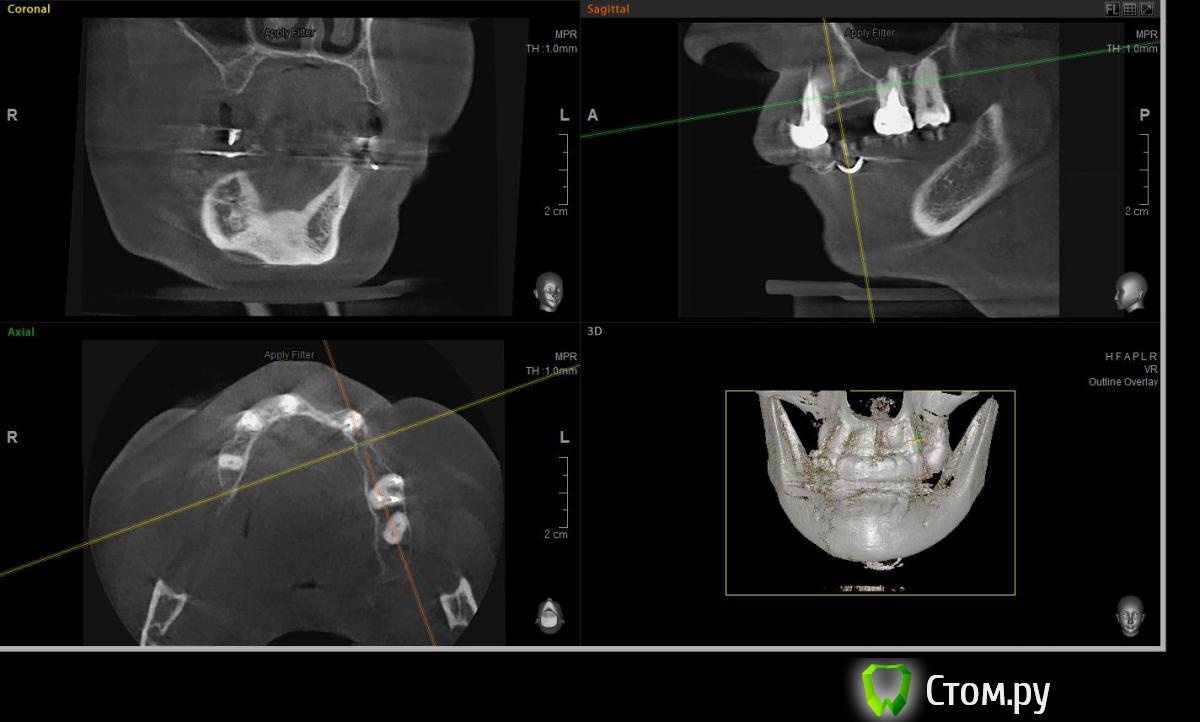

Евгений Ходыкин Опубликовано 22 июля, 2014 Автор Поделиться Опубликовано 22 июля, 2014 Дабы не плодить тем решил очередной случай выложить сюда Решили с пациенткой пока начать с в.ч. В планах имплантация в область отсутствующих 1.6, 1.4, 1.2, 2.1, 2.2, 2.4, 2.5. С 1.6 самому более менее все понятно, мануальных навыков хватит) Прошу помощи коллег относительно остальных областей. Фронт особливо печален... Забегая наперед скажу, что блоки еще не делал. Ауто точно пока брать не планирую, ибо нет даже теоретических навыков. Хочу начать все-таки с аллоблоков. У кого какие будут мнения, заранее спасибо) Ссылка на комментарий